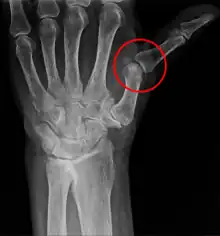

A subluxation is an incomplete or partial dislocation of a joint or organ.[1]

According to the World Health Organization (WHO), a subluxation is a "significant structural displacement", and is therefore always visible on static imaging studies, such as X-rays.[2][3][4]

A subluxation of a joint is where a connecting bone is partially out of the joint.[12] In contrast to a luxation, which is a complete separation of the joints, a subluxation often returns to its normal position without additional help from a health professional.[13] An example of a joint subluxation is a nursemaid's elbow, which is the subluxation of the head of the radius from the annular ligament. Other joints that are prone to subluxations are the shoulders, fingers, kneecaps, ribs, wrists, ankles, and hips affected by hip dysplasia. A spinal subluxation is visible on X-rays and can sometimes impinge on spinal nerve roots, causing symptoms in the areas served by those roots. In the spine, such a displacement may be caused by a fracture, spondylolisthesis, rheumatoid arthritis,[14] severe osteoarthritis, falls, accidents and other traumas.